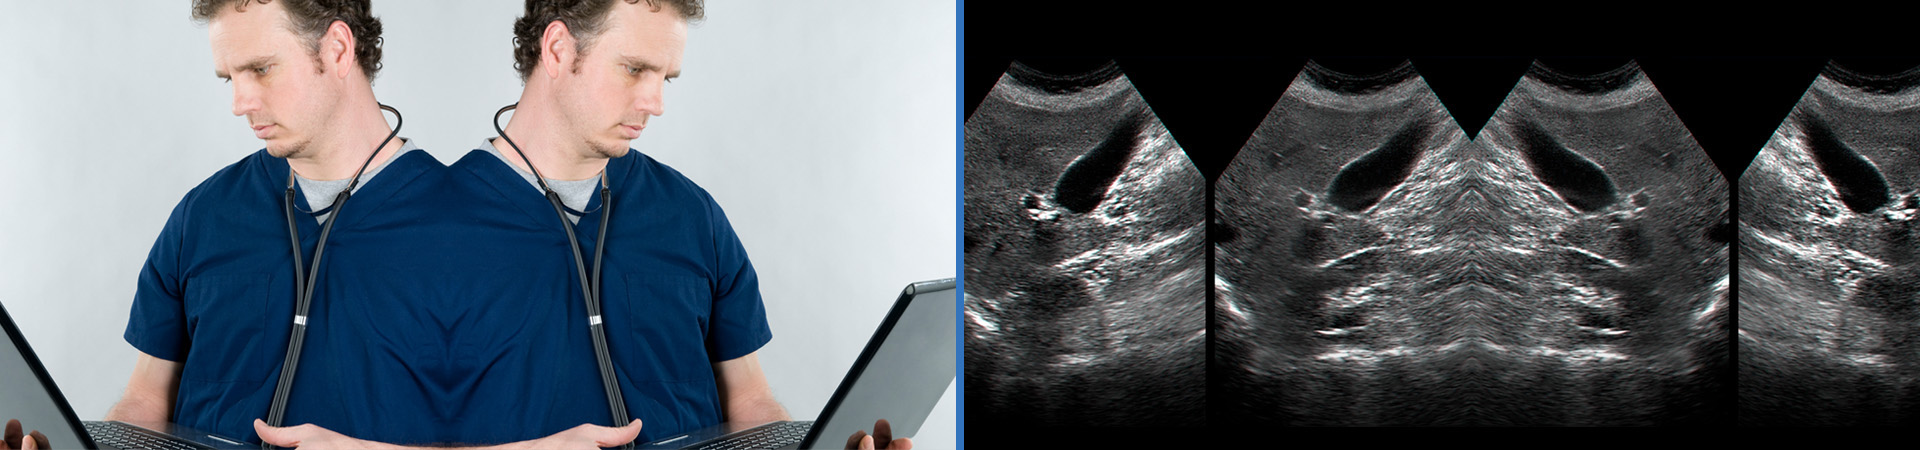

Mobile Ultrasound Limited (MUL) was founded in 1993, as Mobile Ultrasound Imaging, becoming a Limited company in 2004. Then, as now, our aim was to provide a community based Diagnostic Ultrasound service to any sector requiring Diagnostic Ultrasound services.

While there have been many changes in the provision of patient services within General Practice, MUL has continued to provide a high-quality, flexible and cost-effective service, the principal advantages being reduced waiting times, and instant results. Several Practices have worked with MUL continuously since service provision began in 1993. We are a long-standing provider of Ultrasound and Radiography skills to multiple sites within Her Majesty's Prison Service, and both NHS and private hospitals. We also supply ultrasound and echocardiography services to the pharmaceutical clinical trial community.